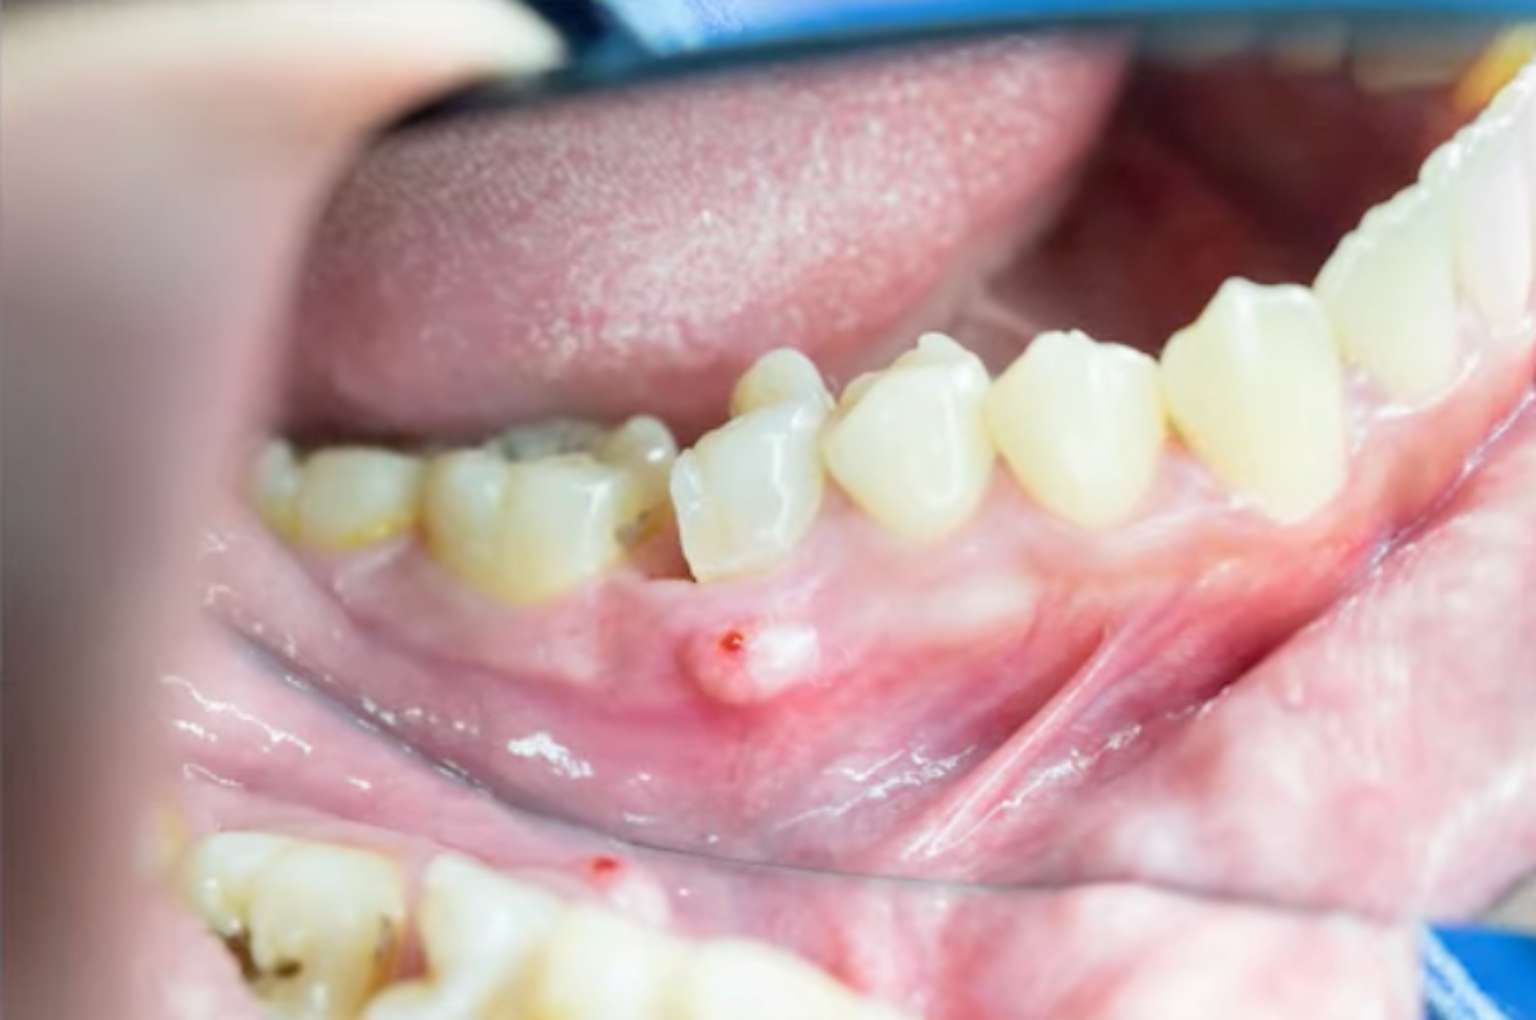

양치질하다가, 혹은 혀끝으로 잇몸을 훑다가 우연히 발견한 볼록한 혹.

손으로 눌러보면 말랑말랑하기도 하고, 터질 듯이 탱탱하기도 합니다. 마치 얼굴에 난 여드름처럼 생겨서 ‘바늘로 콕 찔러서 고름만 짜내면 없어지지 않을까?’ 하는 유혹이 들기도 하고, ‘요즘 야근을 많이 해서 생긴 단순한 혓바늘 같은 거겠지’ 하며 대수롭지 않게 넘기려 하셨을지도 모릅니다.

하지만 잠깐만요! 절대 손대시면 안 됩니다. 지금 여러분 잇몸에 생긴 그 물집은 단순한 피로의 흔적이 아닙니다. 겉보기엔 작아 보이지만, 그 속은 잇몸뼈를 녹이고 있는 무서운 염증의 ‘빙산의 일각’일 수 있기 때문입니다.

치과에서는 이 고름 주머니를 ‘피스텔(Fistula, 누공)’이라고 부릅니다. 이것은 잇몸 겉에 난 상처가 아니라, 치아 뿌리 끝 깊은 곳이나 잇몸뼈 속에서 생긴 고름이 뼈를 뚫고 나오면서 만든 ‘배출구’입니다. 즉, 눈에 보이는 고름을 짠다고 해서 해결되는 문제가 아니라, 땅속 깊은 곳의 원인(뿌리 염증)을 제거해야만 하는 상황인 것이죠.

피스텔(Fistula)은 우리 몸속의 염증(고름)이 밖으로 배출되기 위해 만든 ‘고름 터널의 출구’입니다.

화산이 폭발할 때 지하 깊은 곳의 마그마가 압력을 견디다 못해 분화구를 통해 밖으로 나오는 것과 원리가 같습니다. 치아 뿌리 끝이나 잇몸 뼈 속에서 염증이 생겨 고름이 차오르면, 내부 압력이 높아집니다. 이 고름이 뼈와 잇몸 조직 중 가장 연하고 얇은 쪽으로 길을 뚫고 나오면서 볼록한 주머니를 형성하는 것입니다.

따라서 겉에 보이는 주머니는 결과물일 뿐, 진짜 원인은 잇몸 속, 뼈 내부에 숨어 있습니다.